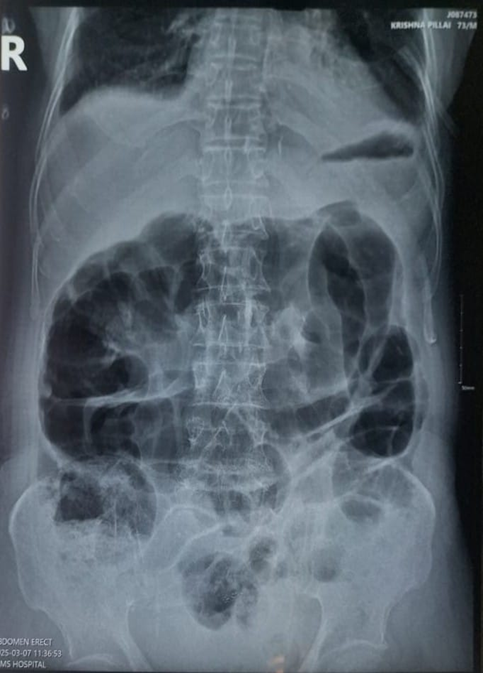

CECT abdomen and pelvis scan was as given in (Figure 1) done for diagnosing pseudomembranous colitis with toxic megacolon  was found out that  edematous bowel wall noted in the ascending colon and descending colon with minimal adjacent fat stranding, normal mucosal enhancement – likely colitis, colonic diverticulosis, mild ascites, atherosclerotic wall thickening in the right distal common iliac artery extending into proximal internal iliac artery causing 70 % luminal narrowing in the right distal common iliac artery and 50 % luminal narrowing in right proximal internal iliac artery.

Figure 1: CECT Scan of abdomen and pelvis